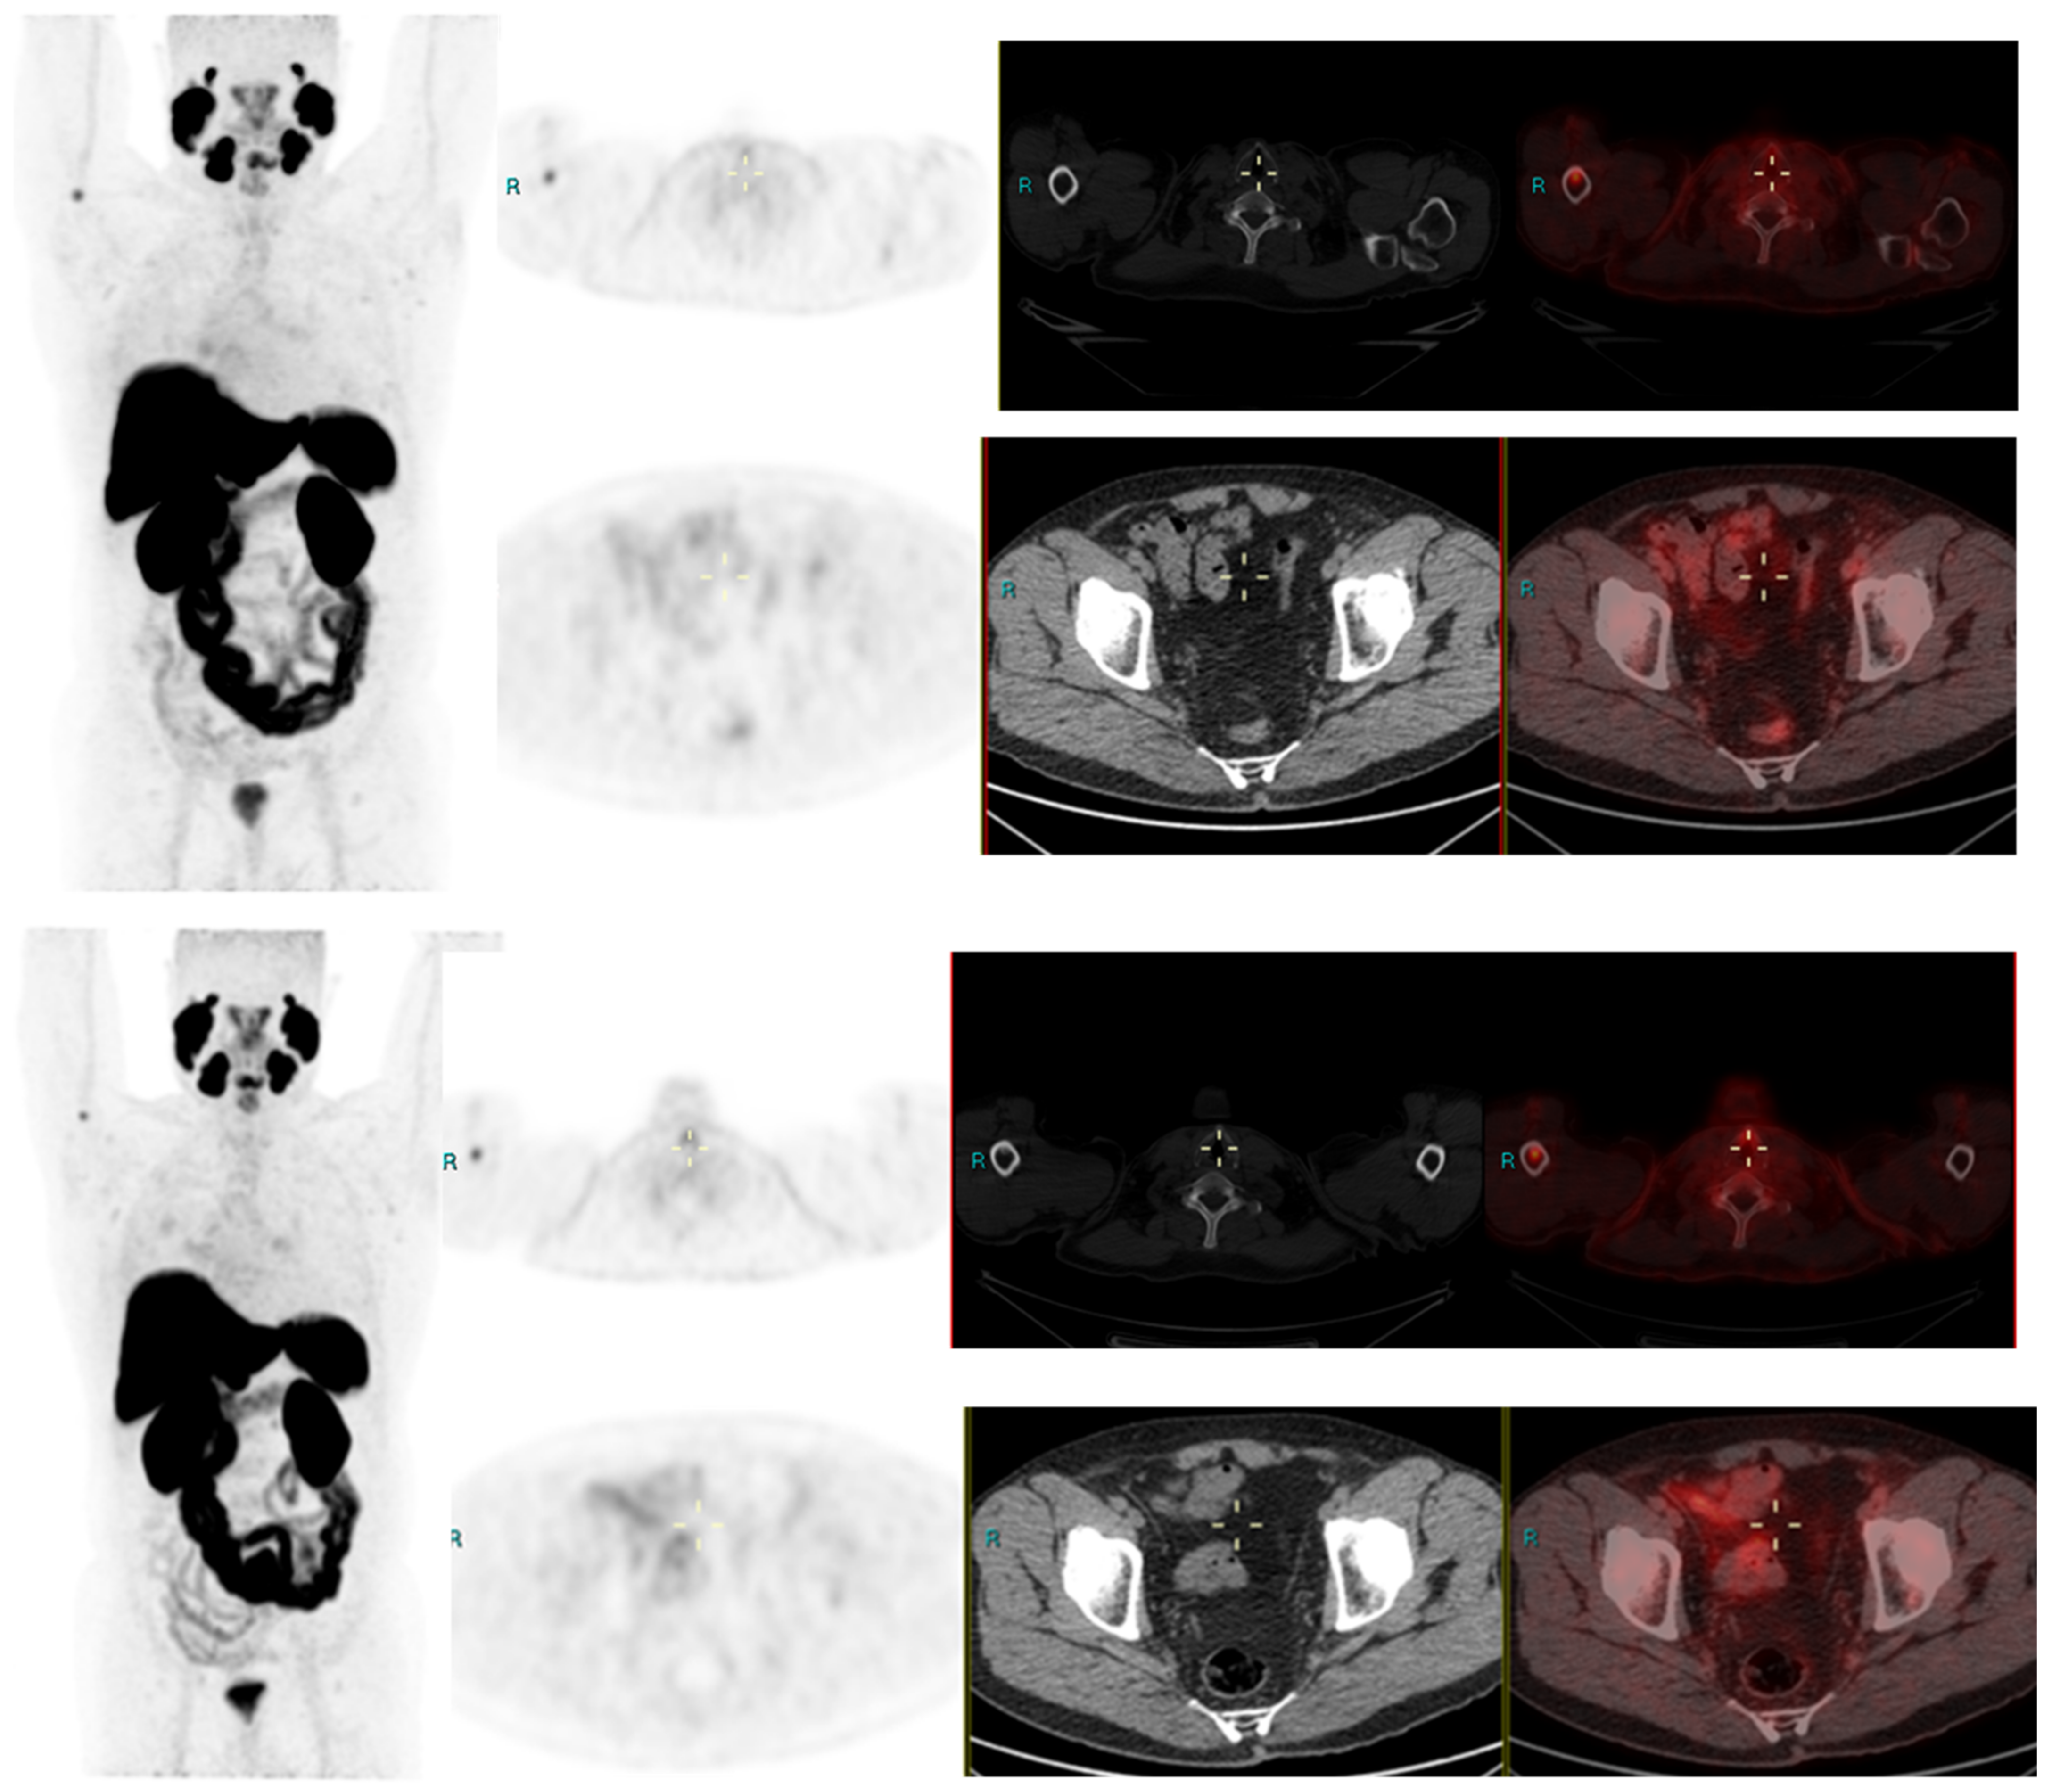

We conducted a separate subgroup analysis of 61 patients (Table 4) who had repeat imaging. Thirty had indeterminate findings on initial PSMA PET CT and the findings changed to a positive lesion in 14 (10 with known small indeterminate pelvic lymph node and four with known indeterminate prostate focus, PSA increase of 0.7 to 3.0 in 6 months), negative in eight (four with pelvic lymph node, four with uptake in bones on prior PET CT, PSA increase of 0.13–2). Six patient had the same indeterminate small pelvic lymph node, two had the same indeterminate retroperitoneal lymph node (PSA increase of 0.4 to 2.5). Overall, the follow-up PSMA PET CT was able to conclude in 24/30 patients on follow-up. Of the 31 patients who had repeat PSMA PET CT scans done for a further rise in PSA levels (PSA rise range 0.3–10), 24 had new lesions (prostate lesion in four, prostate and seminal vesicle involvement in four, pelvic/retroperitoneal lymph nodes in 12, new bone lesion in four) and eight had negative scans even on repeat imaging (PSA rise 0.3–2.3). For example, patient in Figure 2 had negative scan at PSA of 3.4 ng/mL, PSA velocity of 1.3 ng/mL in six months. The uptake in right humerus is at the site of known prior humerus fracture and therefore it was categorized as PSMA RADS 1 B (7). Another patient in Figure 3 had and indeterminate lymph node at PSA 6.5 ng/mL, after rise of 3 ng/mL in 2 years, it was categorized as RADS 3A(7). An interesting finding in this case was the consolidation changes in the right upper lobe, which resolved in a follow-up CT performed after 2 months (Figure 4).

Figure 3.

Radical prostatectomy negative scan at PSA 3.5 ng/mL, indeterminate lymph node at PSA 6.5, rise of 3 ng/mL in 2 years RADS 3A—RP status. Consolidation in right upper lobe. Resolved on follow up CT after 2 months.